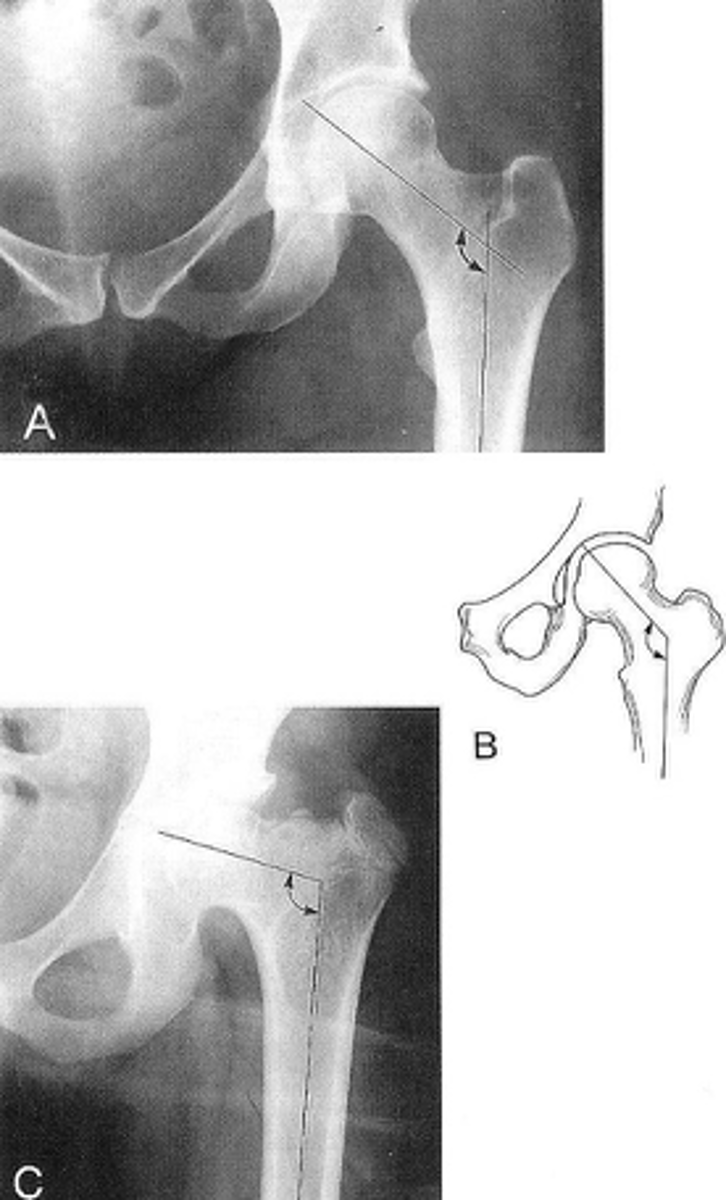

Femoral angle

ID measurement

<p>ID measurement</p>

- AP pelvis

- AP hip

What views are used to measure the femoral angle?

<p>What views are used to measure the femoral angle?</p>

- Mid-axis of femoral shaft

- Mid-axis of femoral neck

- Intervening angle

Femoral angle landmarks

<p>Femoral angle landmarks</p>

120-130˚

Normal femoral angle measurement

<p>Normal femoral angle measurement</p>

Coxa vara

Femoral angle <120˚

<p>Femoral angle &lt;120˚</p>

68

Coxa valga

Femoral angle >130˚

<p>Femoral angle &gt;130˚</p>

69

Klein's line

What views are used to see Klein's line?

<p>What views are used to see Klein's line?</p>

Line along femoral neck

Klein's line landmarks

<p>Klein's line landmarks</p>

Line should intersect portion of femoral head

Klein's line normal measurement

<p>Klein's line normal measurement</p>

Slipped capital femoral epiphysis

Clinical significance of Klein's line

<p>Clinical significance of Klein's line</p>